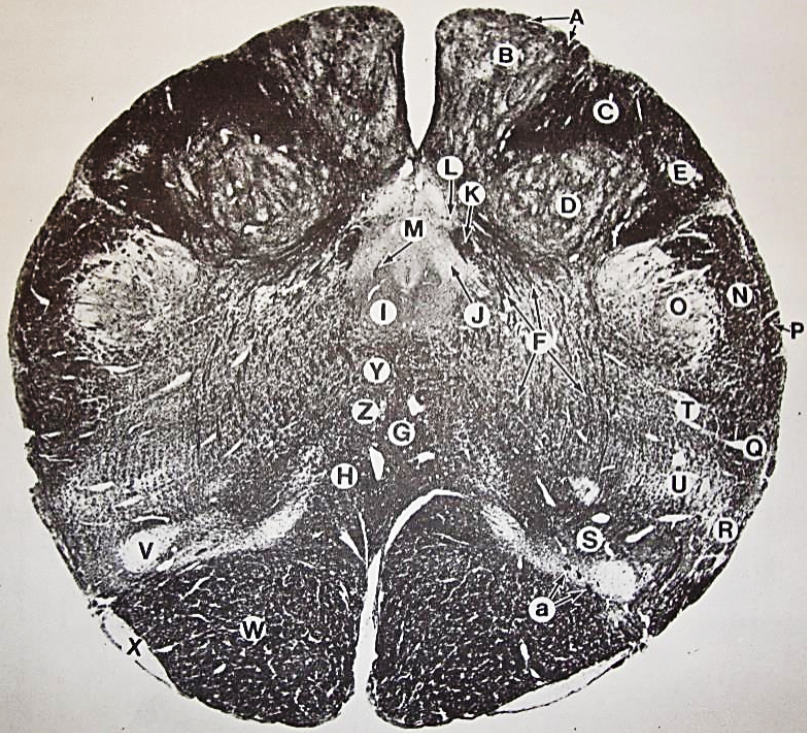

A

Lateral Cuneate nucleus

B

dorsal external arcuate fibers

C + D collectively

vestibular nuclei

C + D collectively

vestibular nuclei

E

dorsal motor nucleus of vagus nerve

F

solitary fasciculus

G

solitary nucleus

H

nucleus ambiguous

I

fascicles of glossopharyngeal nerve

J

hypoglossal nucleus

K

fascicles of hypoglossal nerve

L

dorsal longitudinal fasciculus

M

central tegmental tract

N

inferior olivary nucleus

R

inferior cerebellar peduncle

S

spinal trigeminal tract

T

spinal trigeminal nucleus

U

ventral trigeminothalamic tract

V

pyramidal (corticospinal) tract

W

rubrospinal tract

X

anterior spinocerebellar tract

Y

spinal lemniscus

Z

medial longitudinal fasciculus

a

tectospinal tract

b

medial lemniscus

c

vagus nerve

d

inferior salivatory nucleus